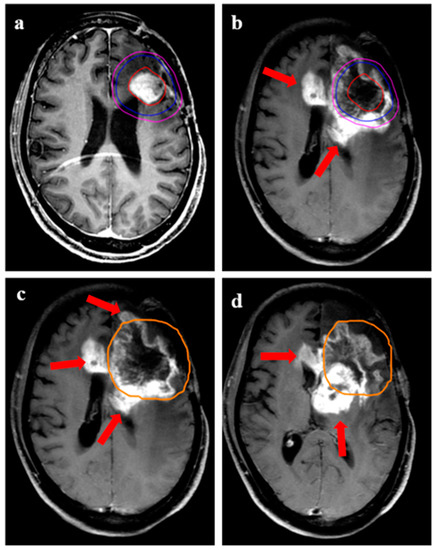

The median time to recurrence was 9 months (range 1–47 months). The progression-free survival at 6 and 12 months was 78% (95% confidence interval (CI) 64–90%) and 38% (95% CI 23–62%), respectively (Figure 1a). The overall survival at 6 months and 12 months was 81% (95% CI 69–94%) and 59% (95% CI 42–74%), respectively (Figure 1b). Representative images for one patient with grade 3 glioma and one patient with GBM are shown in Figure 2 and Figure 3, respectively. During recurrence, the available imaging modality was MRI in 27, PET in 3, and both MRI and PET in 7. Figure 4 shows a patient undergoing surgery followed by radiation (Figure 4c), (postoperative pre-ReRT scan) and ReRT with disease recurrence on MRI and PET. The index area of recurrence (resected and irradiated) over the right frontal-parietal region showed increased contrast-enhancement (4d), which remained non-avid on PET (Figure 4e) (considered radionecrosis), while other enhancing areas over the contralateral periventricular region were showing metabolically active disease (Figure 4e) (distant recurrence). Follow-up scans confirmed the re-irradiated region to represent radionecrosis as it remained stable while the distant disease progressed further (Figure 4f). There was no significant difference in 1-year PFS for patients with or without IDH mutation (30% vs. 32%, respectively, p = 0.85). Given a small number of patients with 1p19q codeletion or known MGMT gene promoter methylation, no separate analysis was undertaken for these groups. The PFS was trending towards significance, favoring better outcomes for patients with gross total resection or subtotal resection compared to biopsy or no surgery, with a 1-year PFS of 40% (95% CI 33–50%) vs. 17% (95% CI 2–32%), respectively (p = 0.06).

Figure 4.

Disease evolution from first progression to subsequent recurrence following re-irradiation in a 25-year female with IDH-mutant grade 3 astrocytoma. (a) shows T1w contrast-enhanced MRI with resection cavity over the right frontal region, with contrast-enhancing recurrent disease seen over the posterior aspect of the cavity (arrow) in (b). Subsequent imaging shows MRI following resection of the disease in (c), which was confirmed as recurrent HGG. (d) shows an enhancing area with central necrosis over the resected and re-irradiated region (8 months following ReRT) over the right frontal-parietal, which was not showing any metabolic uptake on corresponding PET imaging in (e). However, the other area of enhancing nodule over the left periventricular region shows high avidity, considered a distant recurrence. (f) shows MRI performed after 2 months, which confirmed new areas of distant disease, while the re-irradiated region (non-avid on PET) continued to be stable, confirming RT-related changes.

Central, marginal, and distant recurrences were seen in 27 (73%), 4 (11%), and 6 (16%), respectively (Table 3). Of 27 patients with central or in-field recurrence, 14 had more than 50% of the recurrent disease volume within GTV. In the remaining 13 patients, the predominant area of recurrent disease (>50% volume) was seen in the region between GTV and CTV. Figure 5 demonstrates two patients having a central recurrence. In the upper panel, a patient developed recurrence (Figure 5c) within the GTV (contoured based on T2-FLAIR hyperintensity). In the lower panel, the patient developed recurrence primarily beyond the GTV; however, it encompassed the 95% isodose line (Figure 5e,f). Representative images are shown for marginal recurrence (Figure 6) and distant recurrence (Figure 7). Out of six patients with distant disease recurrence in the brain parenchyma, three patients were seen to have leptomeningeal disease (LMD) of disease in the brain. For patients with non-central recurrence, IDH status was known for seven patients, five of whom were mutant.